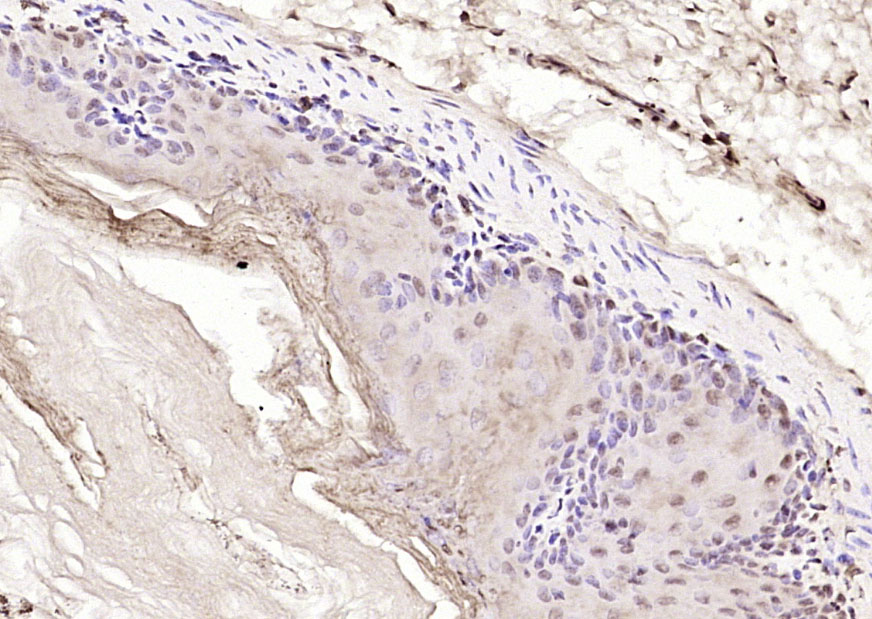

| 英文名称 | RBX1 Rabbit pAb |

| 中文名称 | 环指蛋白75抗体 |

| 产品应用 | IHC-P=1:100-500, IHC-F=1:100-500, IF=1:100-500 Not yet tested in other applications. |

| 交叉反应 | Human, Mouse (Rat, Cow) |

| {IHC-P} | {1:100-500} |